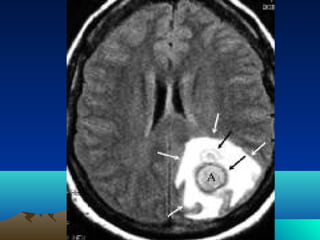

Radiological evaluation

•CT scan

•MRI

Radiological follow-

up

• CT weekly during treatment.

• CT 1 week afterward.

• CT 1 mount then bimonthly…

RESOLVED.

• CT entity 2-3 w.after treatment.

• Mass effect resolved after 3-4 month.

• Contrast in CT until 6-9month.